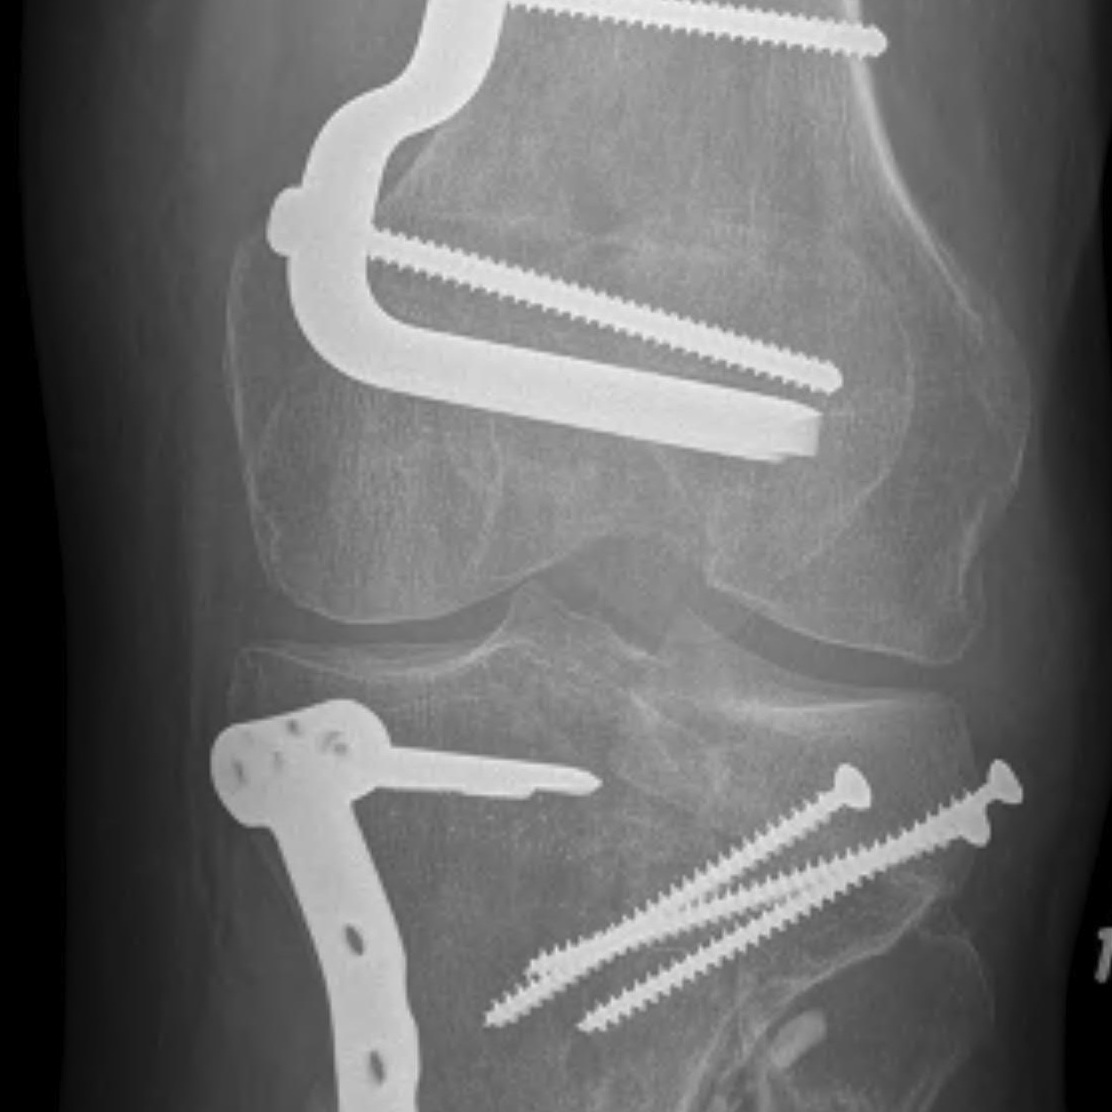

1. Transfibular osteotomy

- incision based on fibular

- divide ITB

- expose CPN under biceps femoris

- release CPN completely from fibular neck and protect

- maintain ligamentous attachments to fibular head

- predrill fibula for later intra-medullary screw

- chevron osteotomy at fibular neck

- reflect fibular head posteriorly and superiorly on biceps / LCL attachments

- place posterolateral buttress plate

- expose anterolateral tibia and place standard anterolateral plate as needed

- stabilize tibio-fibular joint with screws from fibular into tibia / fibular screw